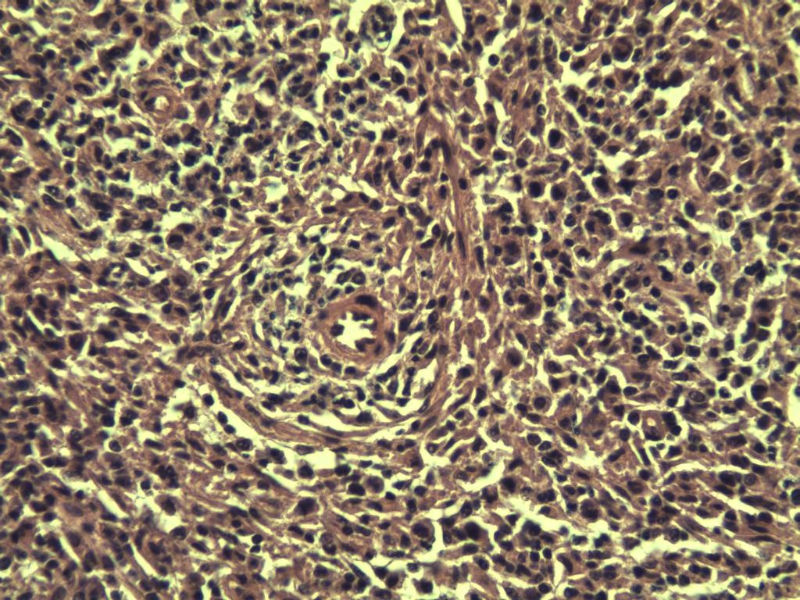

男,38岁,腹股沟 多枚淋巴结活检  直径 0.2-0.5 请各位老师看看 是什么 谢谢了!

"畏寒,发热咳嗽1年,加重伴腹部疼痛2月" 2月前患者感腹部疼痛不适伴大便呈稀大便,量不详,伴腰骶部疼痛,胸片:纵膈及右肺门多发性淋巴结肿大,进一步完善胸部CT:右肺及中叶病变,纵膈及肺门多发淋巴结肿大,结核性可能,脾脏增大,PPD(-),1个月来患者出现中上腹食欲不振,体重进行性消瘦,全身疲乏无力,3天前到医学院就诊,腹部B超:右肝囊肿,胆囊壁毛糙,脾大,胰周多个减弱回声,淋巴结不能除外,腹水,血常规示:WBC16.36x109 /L,N%14.25%,RBC2.63x1012/L ,HGB 66g/L 。右侧腋窝及腹股沟可扪及多枚淋巴结,压痛,无明显粘连。

腹股沟 多枚淋巴结活检图1

副皮质区增生,纤维化显著,细胞呈多形性,有一些多核巨细胞及一些异型细胞,病理性核分裂易见,胞浆红染,散在的小淋巴细胞,T细胞淋巴瘤不能除外,树突细胞肉瘤等鉴别。免疫标记。CD21、CD3、CD5、CD10、CD20、CD79a、PD1、CD68、CXCL13、KI-67、CD68、CD163等,据切片选择。不知对否。

淋巴结正常结构破坏,可见大的异型细胞,上皮样或梭形,恶性肿瘤,依据病史,首先考虑淋巴造血系统疾病,大中小细胞混杂,大细胞多,形态多样,可见多核瘤细胞,除以上考虑外需鉴别间变大、组织细胞肉瘤、指状突/树突细胞肿瘤、HL等,还需排除肉瘤或癌转移,尽管病人年轻,加上ALK、CK、S-100、CD1a。